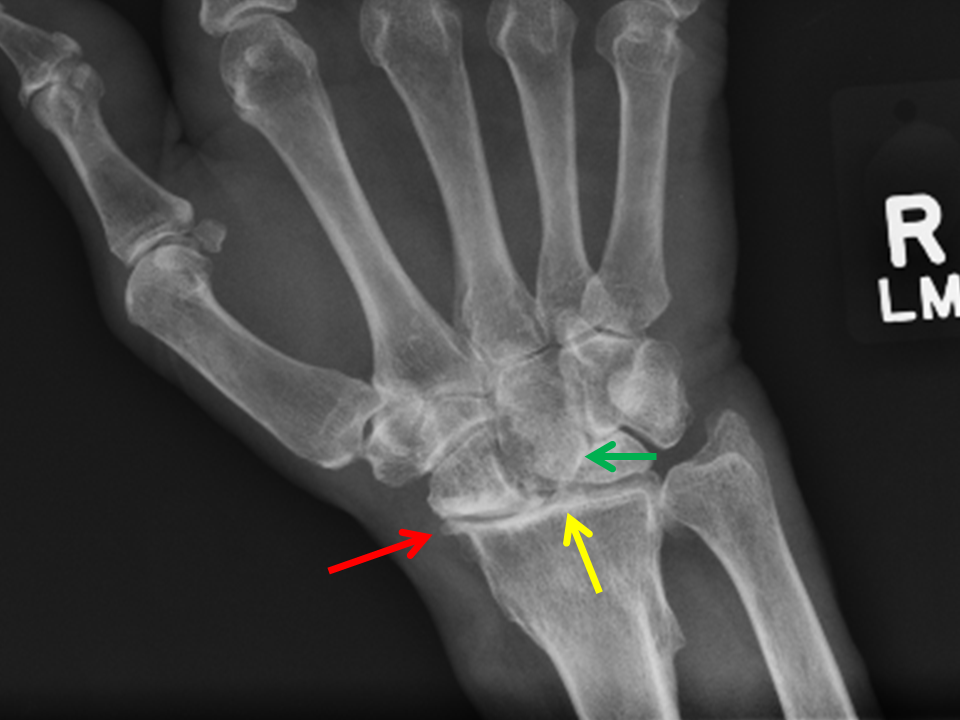

Радиоульнарный угол

Радиоульнарный угол 137 фото